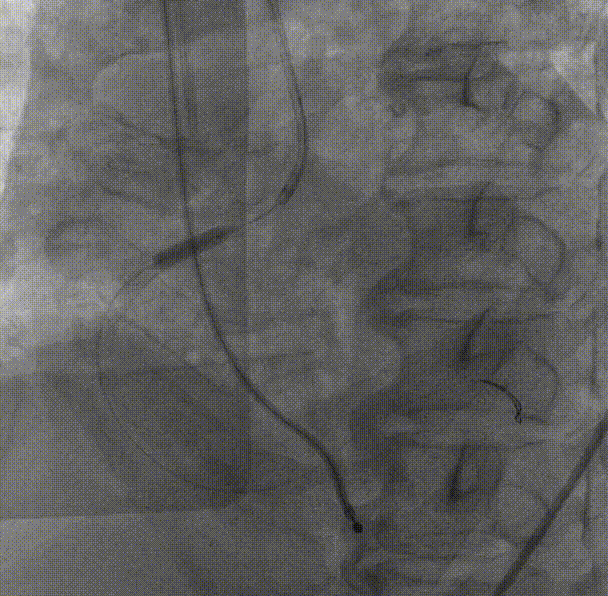

入路造影评估 正中穿刺

CAG:左主干前三叉真性分叉病变,病变钙化明显,左主干末端狭窄约85%,前降支近段狭窄70-80%,中段长弥漫狭窄60-70%,回旋支开口狭窄60-70%,近中段狭窄80-90%;右冠近段狭窄80-90%,中段狭窄85%,远段狭窄50%。考虑患者胸痛症状可能为冠心病+AS共同作用,以及患者冠脉病变钙化严重,予以PCI+TAVR一站式处理。

右冠中段开口予Balloon Trek2.5*15mm预扩;于中段至开口依次植入Integrity stent3.5*30mm;Integrity stent3.5*22mm;支架内予Balloon NC Trek3.5*12mm后扩。

回旋支中段予Balloon Trek2.5*15mm预扩,回旋支近中段植入3.0*36mm支架;支架内予Balloon NC Trek3.5*15mm后扩;左主干-前降支近段病变予Balloon Trek2.5*15mm预扩;于左主干-前降支近段植入Integrity Stent3.0*26mm;前降支支架内予Balloon NC Trek3.5*12mm后扩,回旋支开口无受压,远端血流TIMI3级。

复查冠脉造影结果满意。